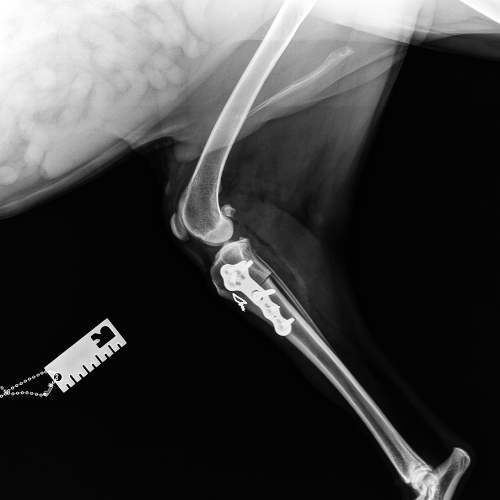

El servicio de traumatología está dirigido por Enrique Senís, especialista en traumatología y ortopedia por la Universidad Complutense de Madrid . Estamos orientados al diagnóstico y tratamiento de patologías del sistema musculoesquelético, incluyendo fracturas, luxaciones, rotura de ligamento cruzado y demás alteraciones articulares y deformidades óseas.

Disponemos de medios diagnósticos avanzados y aplicamos técnicas quirúrgicas de última generación en osteosíntesis, estabilización articular y corrección de deformidades, con el objetivo de restaurar la funcionalidad y minimizar el dolor en nuestros pacientes.